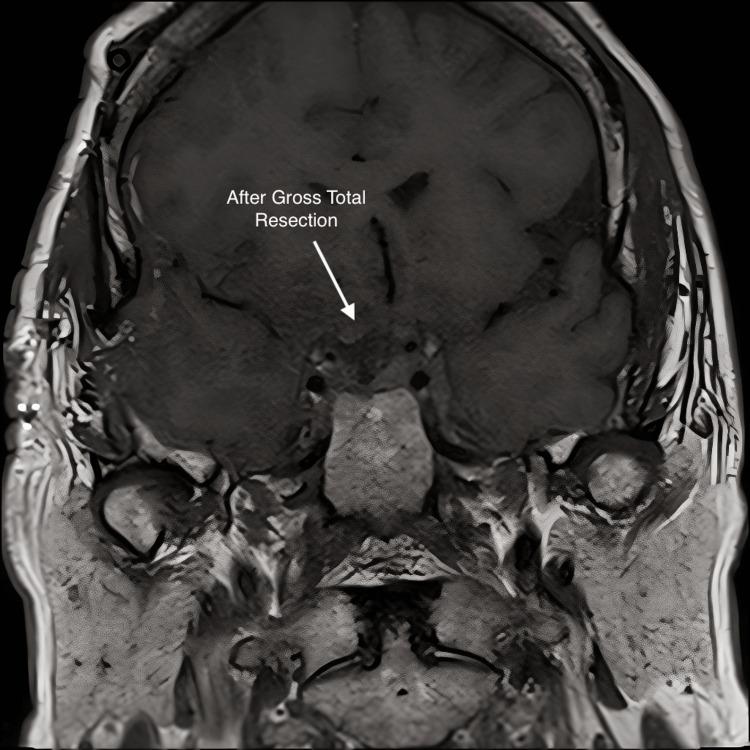

Craniopharyngiomas are rare epithelial malformations in the sellar or suprasellar regions of the craniopharyngeal ducts. Complete surgical resection is difficult due to the location of the base of the skull and the risk of injury to vital neurological structures. Fractionated radiation is effective in controlling residual tumors, but craniopharyngiomas can progress during treatment. The papillary subtype is driven by BRAF V600E mutations. Treatment with BRAF and MEK inhibitors alone has a response rate of 90% but a median progression-free survival of only 12 months. A 57-year-old female presented in May 2017 with complaints of headaches and blurriness in her right eye. Brain MRI demonstrated a 2 cm suprasellar mass engulfing the right optic nerve and optic chiasm. The patient underwent a transsphenoidal hypophysectomy with pathology consistent with a benign pituitary adenoma. Follow-up imaging in August, however, showed recurrence, and a re-resection was performed which surprisingly demonstrated papillary craniopharyngioma. Due to subtotal resection, the patient elected to proceed with intensity-modulated radiation therapy (IMRT) to the tumor bed in April of 2018 with an intended dose of 5400 cGy. After treatment with 2160 cGy in 12 fractions, the patient experienced visual deterioration and progression of the cystic tumor. The patient underwent another debulking procedure but due to rapid recurrence, an endoscopic transsphenoidal fenestration was performed. On postoperative imaging, a cystic mass was still engulfing the right optic nerve and chiasm. Due to the extended break and limited radiation tolerance of the optic chiasm, we elected to re-treat the tumor with an additional 3780 cGy IMRT in conjunction with one cycle of Taflinar and Mekinist, which was completed in August 2018. The cumulative dose to the optic chiasm was 5940 cGy.The patient had an excellent clinical response to treatment with the improvement of vision in her right eye. A brain MRI on 3/29/2019 demonstrated no residual craniopharyngioma. Four-year follow-on CT scan showed no evidence of tumor recurrence. The patient had preservation of vision and did not suffer any late neurological toxicity or new endocrine deficiency. Surgical resection and radiation were ineffective at treating our patient's craniopharyngioma due to rapid cystic progression. This is the first case report in the literature detailing concurrent radiation therapy with BRAF and MEK inhibitors for papillary craniopharyngioma. Despite a suboptimal dose of radiation, our patient had no tumor recurrence and no late toxicity four years after treatment. This represents a potentially novel treatment strategy in this challenging entity.

颅咽管瘤是颅咽管蝶鞍区或鞍上区罕见的上皮性畸形。由于颅底位置以及损伤重要神经结构的风险,完整手术切除困难。分次放疗对控制残留肿瘤有效,但颅咽管瘤在治疗过程中可能进展。乳头状亚型由BRAF V600E突变驱动。单独使用BRAF和MEK抑制剂治疗的缓解率为90%,但无进展生存期的中位数仅为12个月。一名57岁女性于2017年5月因头痛和右眼视物模糊就诊。脑部MRI显示鞍上有一个2 cm肿块,包绕右侧视神经和视交叉。患者接受经蝶窦垂体切除术,病理结果符合良性垂体腺瘤。然而,8月的随访影像学检查显示复发,遂再次进行切除,结果令人惊讶地发现是乳头状颅咽管瘤。由于次全切除,患者于2018年4月选择对瘤床进行调强放疗(IMRT),计划剂量为5400 cGy。在给予12次分割共2160 cGy治疗后,患者出现视力恶化和囊性肿瘤进展。患者又接受了一次减瘤手术,但由于复发迅速,进行了内镜经蝶窦开窗术。术后影像学检查显示,一个囊性肿块仍包绕右侧视神经和视交叉。由于视交叉放疗中断时间延长且耐受性有限,我们选择在2018年8月对肿瘤再次进行3780 cGy的IMRT治疗,并联合一个周期的达拉非尼和曲美替尼,视交叉的累积剂量为5940 cGy。患者对治疗有良好的临床反应,右眼视力改善。2019年3月29日的脑部MRI显示无残留颅咽管瘤。四年后的CT随访扫描未发现肿瘤复发迹象。患者视力得以保留,未出现任何晚期神经毒性或新的内分泌功能减退。由于囊性肿瘤迅速进展,手术切除和放疗对我们这位患者的颅咽管瘤治疗无效。这是文献中首例详细描述乳头状颅咽管瘤同步放疗联合BRAF和MEK抑制剂治疗的病例报告。尽管放疗剂量不理想,但我们的患者在治疗四年后无肿瘤复发且无晚期毒性。这代表了在这个具有挑战性的疾病中的一种潜在新治疗策略。